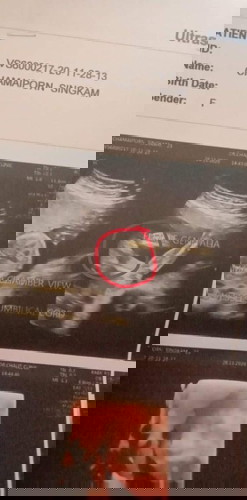

ไปซาวเพศมาหมอบอกว่าน่าจะผู้หญิงเห็นเหมือนมี3ขีด ดูใบซาวแล้วมีโอกาศดูผิดไหมค่ะ ลูกอยู่ท่าเอาหัวลงขาชี้ฟ้าค่ะ

ดูภาพก็น่าจะ ญ คะแม่